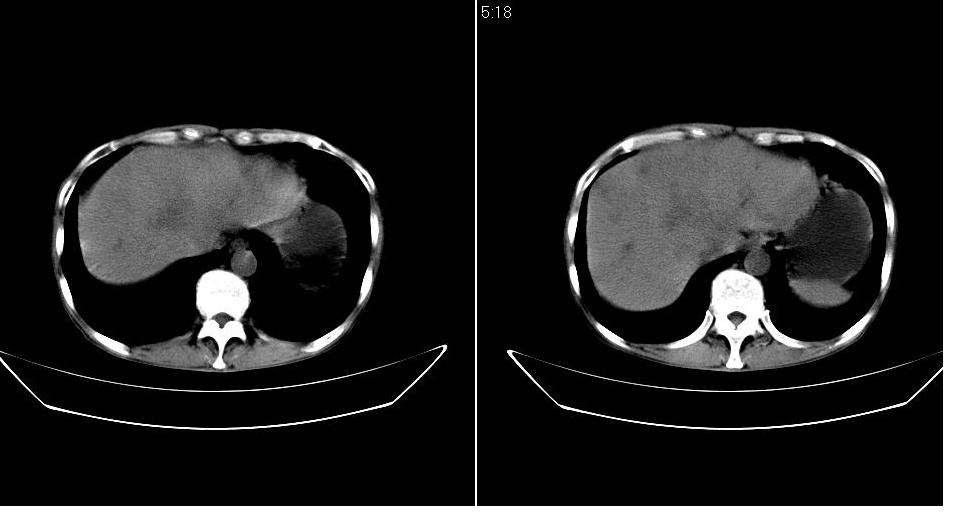

男 55岁,黄染二十余天,无明显腹疼及发热,病人拒绝增强,因没钱.

考虑壶腹周围ca办阻塞性胆道系统扩张、肝转移。 强烈要求增强!

考虑胰头ca伴阻塞性胆道系统扩张、肝转移。建议增强!

考虑胰头癌伴肝门部淋巴结转移及胆管扩张或是肝门部胆管癌伴胰头周围淋巴结转移.

考虑胰头癌伴肝门部淋巴结转移、肝脏转移及胆管扩张。

胰头增大,密度稍低,胰腺体尾部缩小,肝内胆管明显扩张,肝右叶低密度影。 考虑胰头癌并阻塞性肝内胆管扩张,肝内转移灶?建议进一步增强扫描。